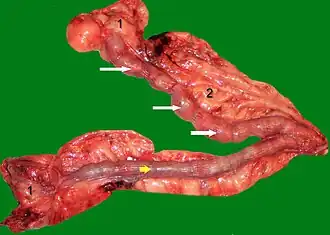

Pathologisch-anatomisch sind die Gebärmutterhörner verdickt (1 bis 3 cm) und es finden sich 1 bis 7 mm große Zysten.